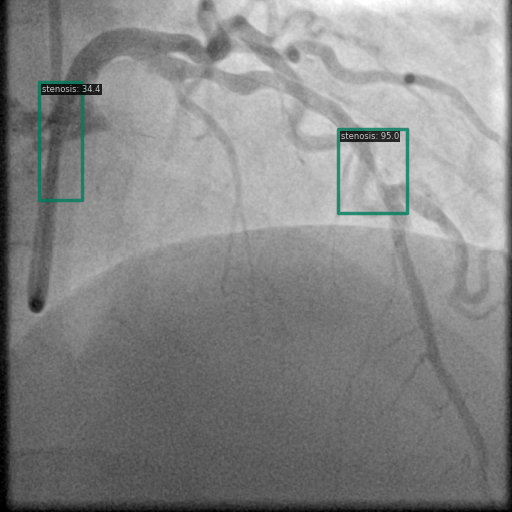

Figure 1 shows sample images from the ARCADE dataset with annotations for stenosis detection. The annotations highlight regions of arterial narrowing, providing ground truth data for training and evaluating object detection models.

To further assess the detection performance, qualitative results for three test images are presented in Figure 2. The first column shows the original images with ground truth annotations. The second, third, and fourth columns depict detections from DINO-DETR, Grounding DINO, and YOLO, respectively.

(a) Original (b) DINO-DETR (c) Grounding DINO (d) YOLO

The qualitative comparison in Figure 2 reinforces the trends observed in the quantitative evaluation. DINO-DETR produced fewer detections, occasionally missing relevant stenotic regions, consistent with its conservative detection strategy aimed at minimizing false positives [6]. Grounding DINO, although capable of identifying more regions, sometimes resulted in cluttered predictions due to over-detections [7]. YOLO provided a reasonable trade-off by effectively capturing anatomical structures while maintaining relatively high confidence scores and clear visualizations [5].